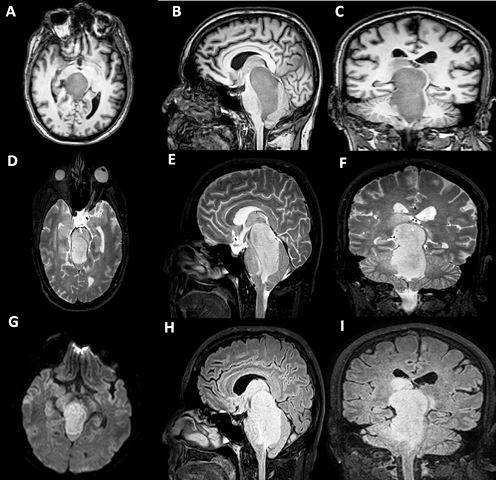

Se realizó estudio por resonancia magnética donde se observó secuencias de 3D en T1, T2, FLAIR, difusión y SWI en la que se observó lesión ocupativa hiperintensa en T2 e hipointensa en T1 que ocupa el acueducto de Silvio, IV ventrículo, y se identifica la glándula pineal a la cual desplaza en sentido dorsal; marcados signos de restricción de la difusión, no calcificaciones y escasos signos de angiogénesis; no hidrocefalia; aracnoidocele selar; signos de edema en región talámica bilateral con predominio derecho, así como signos de degeneración walleriana derecha. (Figura 1)

La evolución del paciente a los 6 meses de operado fue satisfactoria, lo cual se observó en la imagen de resonancia magnética (IRM) mostrando control de la lesión. (Figura 5)